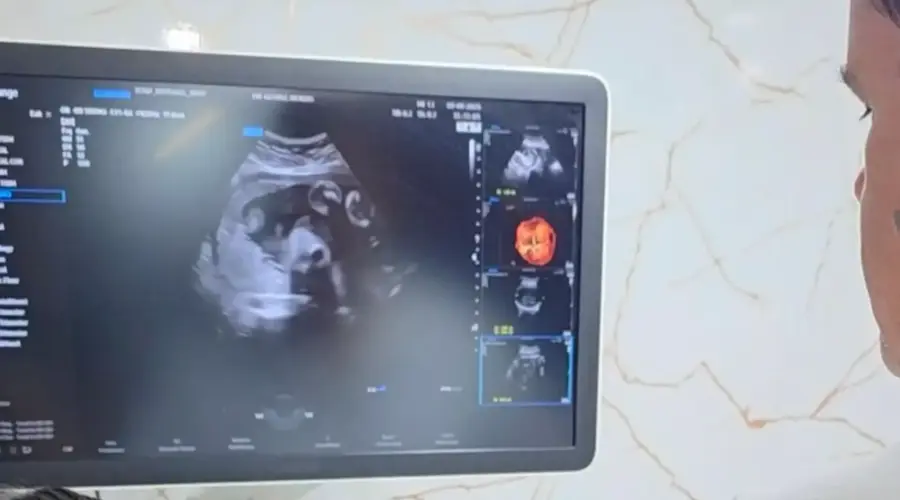

Os atendimentos acontecerão no Paço Municipal Laurentino Martins, na prefeitura, com distribuição de senhas a partir de 05h30 às 07h00 da manhã. Entre os exames oferecidos estão; ultrassonografia obstétrica, abdome superficial, abdome superior (com jejum de 12 horas), próstata (com bexiga cheia), endovaginal, bolsa escrotal, tireoide e mama. Cada paciente poderá realizar um exame.